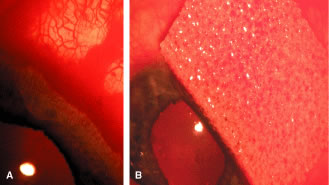

To obtain increasingly lower IOP, it is necessary to modify surgical technique (Table 15). By performing guarded filtration procedures so that the sutures can be released postoperatively, with the use of either laserable or releasable sutures, a lower final IOP can be obtained in some cases. This technique allows a bleb to develop that is similar to that seen in a full-thickness filtration procedure. Such blebs tend to be thin, polycystic, and located directly at the limbus, in contrast to those seen after classic trabeculectomy, which are thicker, lower, more diffuse, and more posterior. When antifibrosis agents (antimetabolites and corticosteroids) are added to procedures designed to develop full-thickness filtration, IOP tends to be sharply reduced.27–29 The blebs associated with the use of 5-fluorouracil (5-FU) and mitomycin are an exaggeration of the full-thickness type of bleb: Often, they are extensive, sometimes involving 360 degrees of the anterior surface of the globe, and the conjunctiva tends to be thin and completely ischemic.30–34

The thin filtration blebs associated with the use of mitomycin or 5-FU may rupture spontaneously. They tend to be so high that the adjacent cornea becomes dry, with the development of an uncomfortable delle. Ptosis tends to develop, and patients often are photophobia One of the most serious concerns is the high incidence of endophthalmitis in patients with thin blebs. When full-thickness blebs were the routine type of glaucoma procedure, endophthalmitis would develop in approximately 1% of patients. When 5-FU was used to develop filtration blebs inferiorly, an 8% rate of endophthalmitis was reported.35–42 Hypotony, even in the absence of a thin bleb, introduces serious problems. The soft eye does not maintain a constant optical state, and it has a constantly changing amount of astigmatism that makes it impossible to correct. Each time the patient blinks, the amount of astigmatism changes. Macular and disc edema cause reduced central acuity and deterioration of the visual field, and the globe may have a constant, visceral ache. Patients with such eyes are not comfortable.